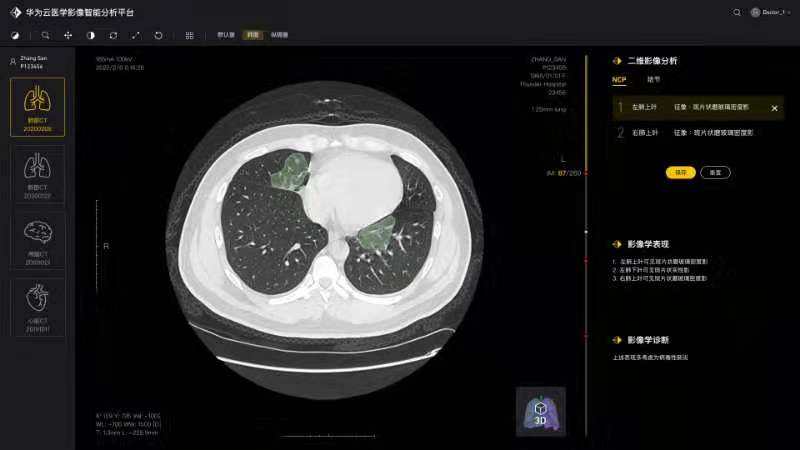

将论文写在祖国的大地上,加快加强疫情防控科研攻关,服务一线疫情防控救治——疫情发生以来,由学院白翔、许永超等老师负责的91论坛

—华为智能创新实验室积极发挥自身优势,组织团队师生争分夺秒抓紧开展高质量科研攻关,与附属协和医院放射科、华为云、篮网科技等团队共同研发出一套基于人工智能技术的面向新冠肺炎肺部CT影像量化分析系统。2月29日下午,中共中央政治局委员、国务院副总理孙春兰率中央指导组来校考察疫情防控科研攻关情况,许永超副教授当场向孙副总理介绍了研发推出该系统的工作及成果。该系统可以辅助医生更高效地区分新冠肺炎的早期、进展期与重症期,有利于早期筛查与防控。同时,对于确诊病人,基于对多次复查影像数据的量化分析,医生能够有效评估病情进展及用药疗效等情况。目前该系统已在全国几十家医院使用,日均调用量3000多次。孙春兰肯定了研究团队所开发系统的精确性,可以辅助医生定量分析,大幅提升效率,缓解影像医生的压力。她非常关注该系统的落地应用情况,特别是在湖北省、武汉市的应用,鼓励团队结合CT影像与核酸试剂等信息,进行更为精准的新冠肺炎诊断。